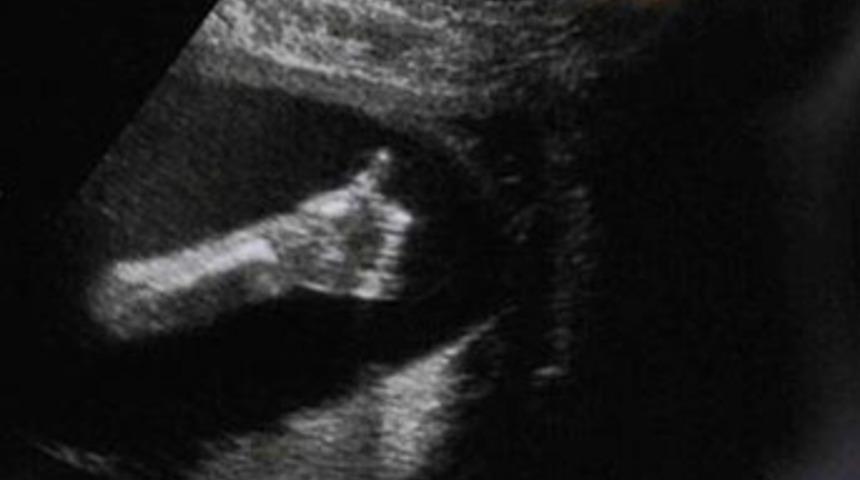

Üçüncü ultrason muayenesi hem yüreklere su serpti hem de hoş bir sürpriz yaptı. Bebeğin ultrasondan yansıyan fotoğraflarıyla annesine baş parmağını yukarı kaldırıp 'herşey yolunda, ben iyiyim' mesajı verdi.

Aldıkları haberle rahatlayan Donna Sayer, "Başta çok endişeleniyordum. Ancak şimdi herşey yolunda gittiği için çok mutluyum. Bebeğimin 'ben iyiyim' mesajlı fotoğrafını aileme ve arkadaşlarıma göstermek de keyif veriyor." dedi.